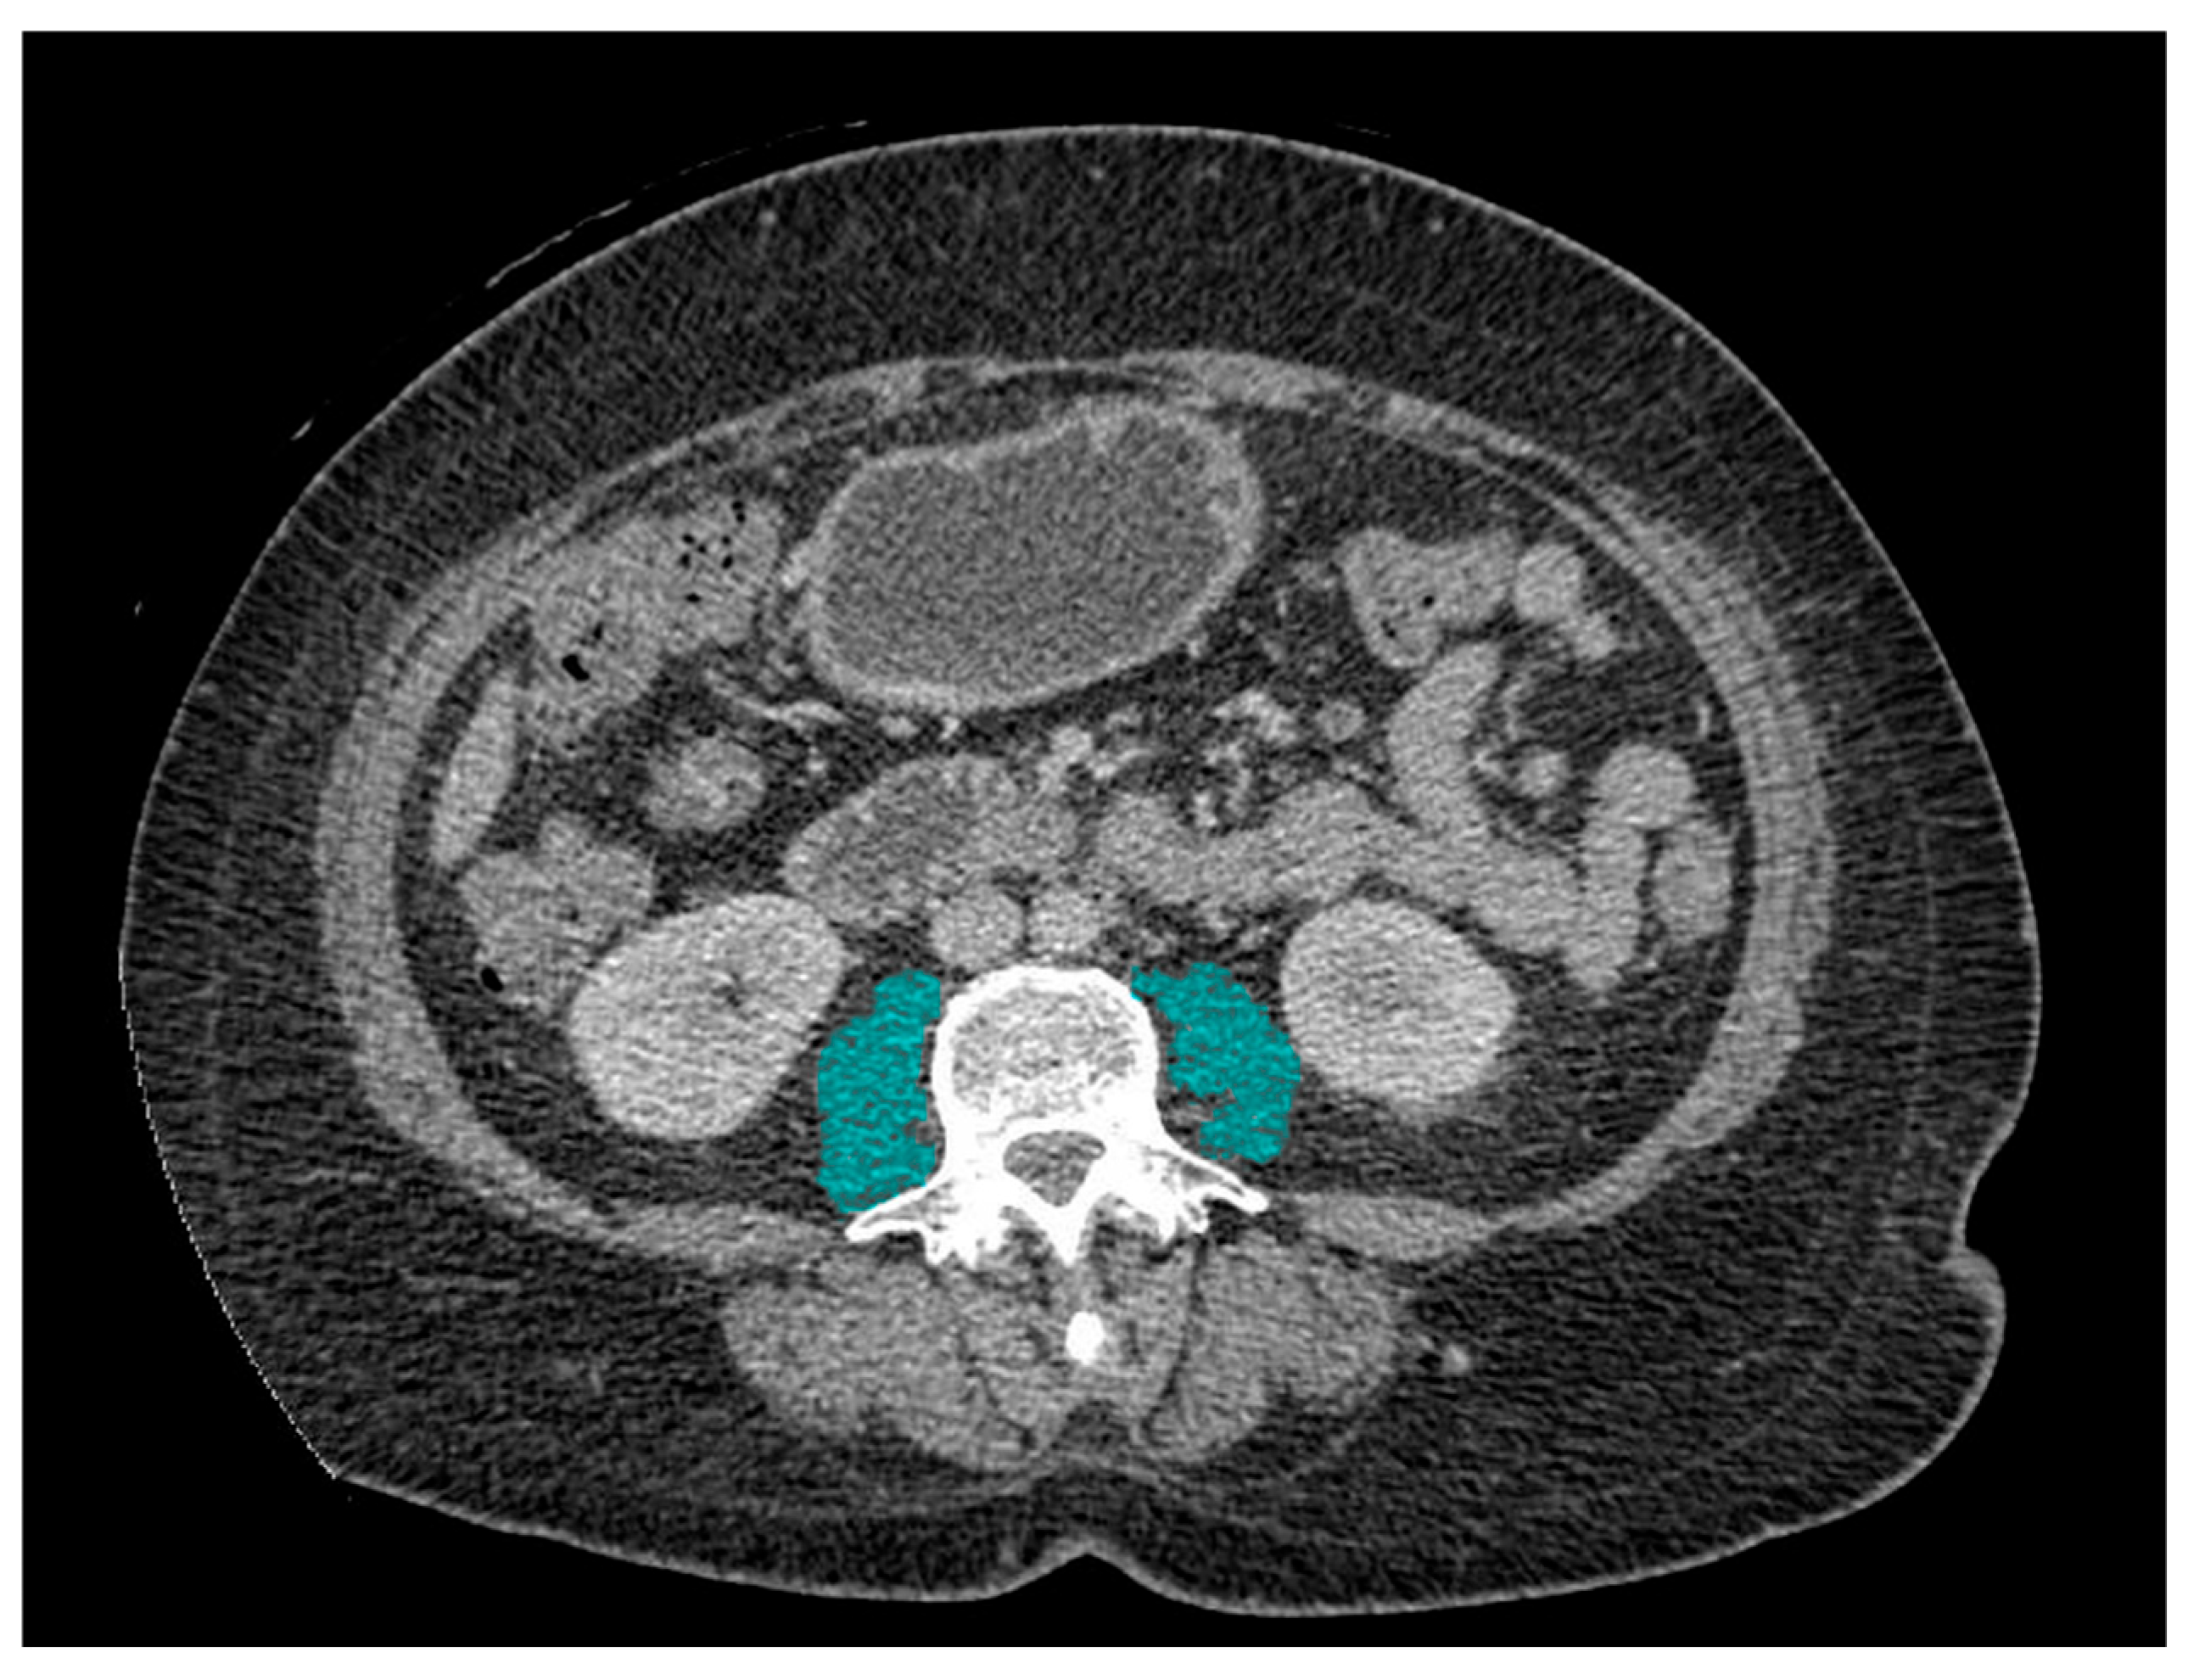

2.1. Definition of Sarcopenia